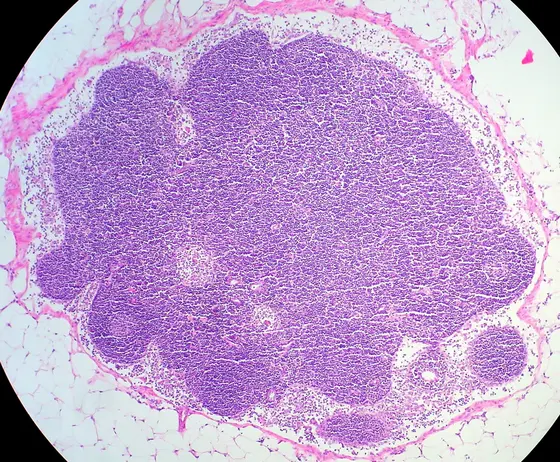

Mikroskopische Aufnahme eines Gewebes mit einer großen, lila gefärbten Zellansammlung, umgeben von helleren, fettigen Bereichen. Die Struktur zeigt eine dichte, homogene Massenanordnung, die auf histologische Merkmale hinweist.

Gewebeschnitt durch eine Lymphknoten